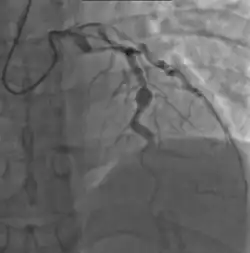

Kawasaki Disease causes inflammation of arterial walls throughout the body. This disease also affects skin, mucous membranes, and the body's lymph nodes.[2][3][4] Baker's lab is investigating the possibility of a viral causative agent for the disease. This disease mostly affects children under the age of 5. Causes remain unknown, however it is treatable within days if the symptoms are recognized early enough. If left untreated, it can lead to serious problems for the heart.[5]